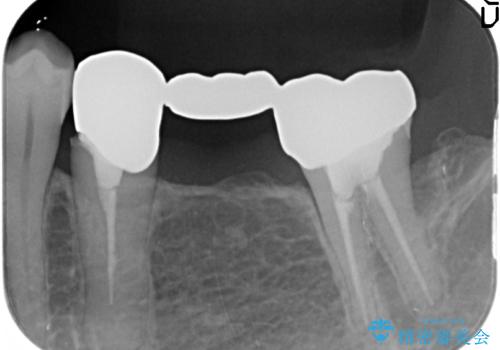

- 他院にて左下奥歯のポケットが深いと言われた、銀歯と歯茎の隙間も気になるのでまとめて治療して欲しいと来院された方の症例です。

左下7の遠心部は部分的な骨欠損によるポケットが10mmあったため、再生療法による骨の再生を行いました。

骨の定着を待ちポケットが3mm(正常範囲内)であることを確認後、オールセラミッククラウンによる欠損補綴を行いました。